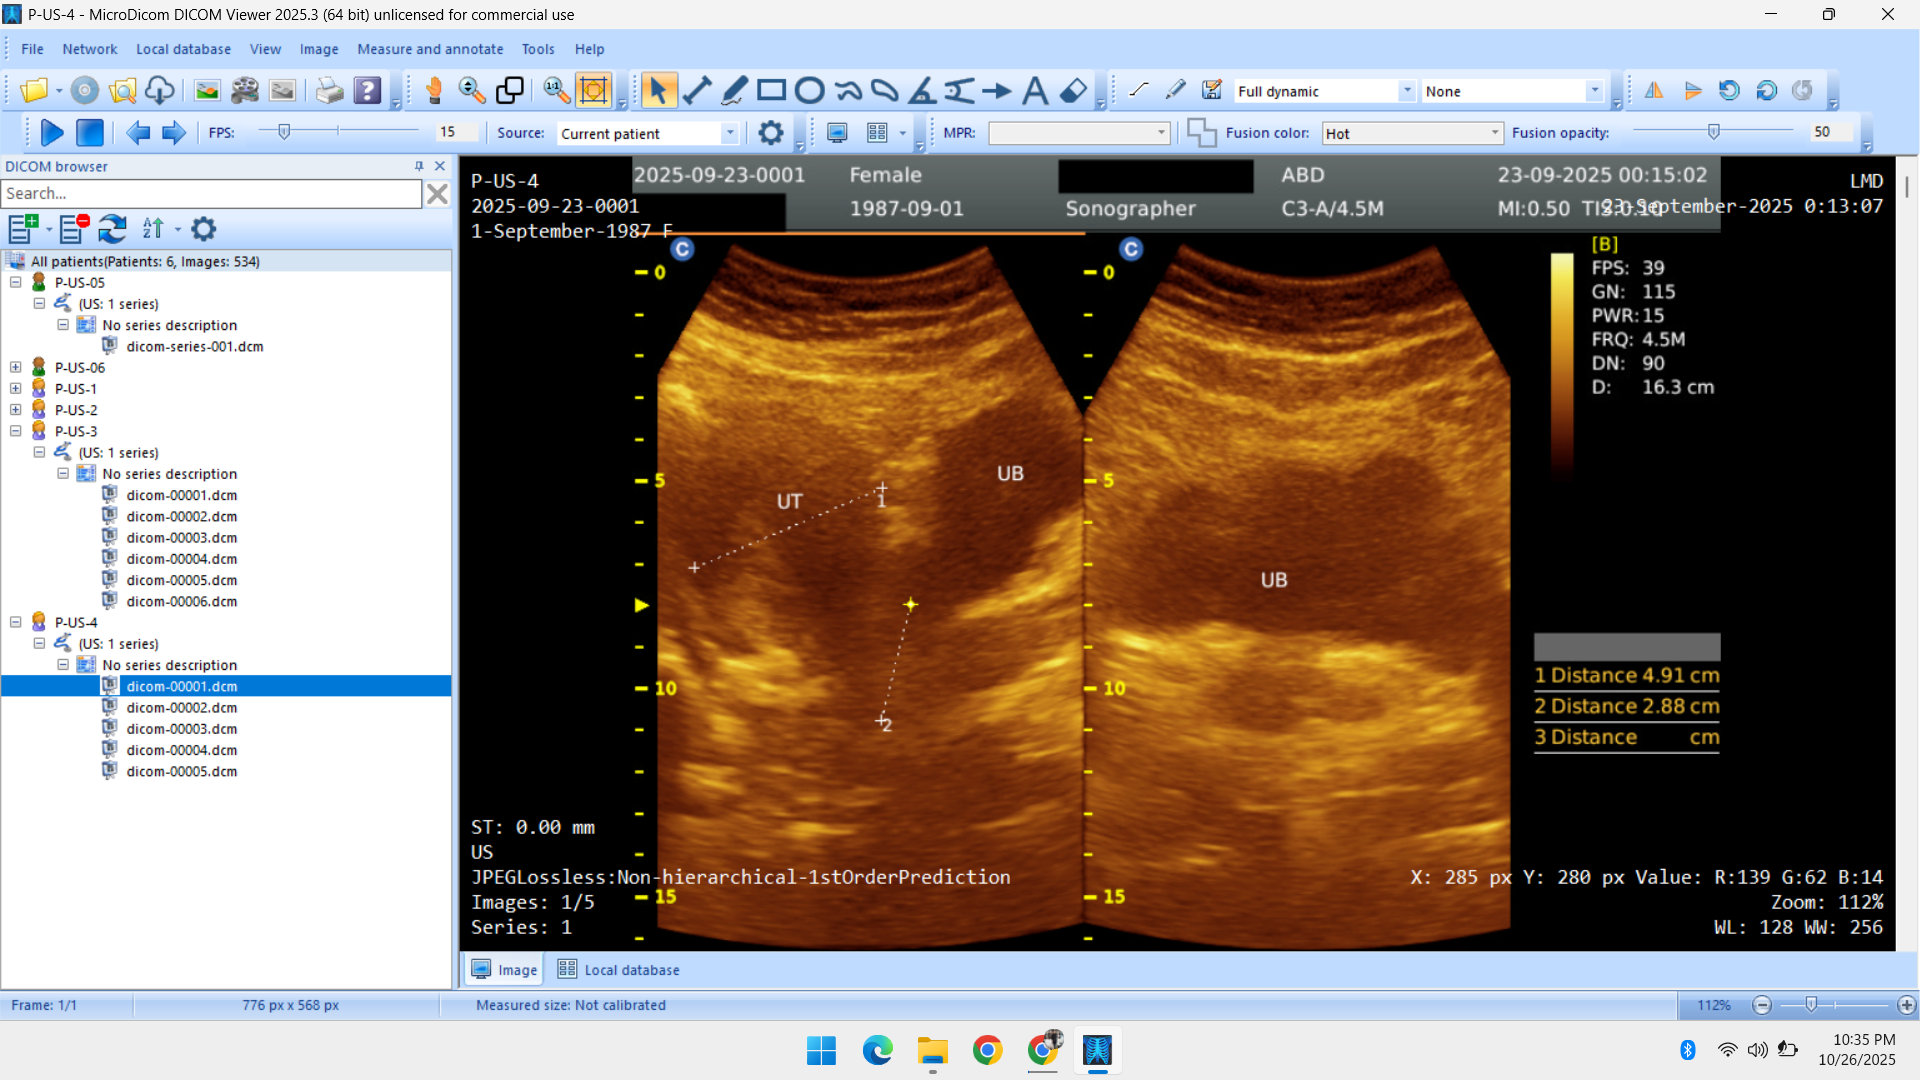

- Radiology Data – CT Scans, X-Rays, MRI, Echocardiography, Ultrasound.

Healthcare & Medical Data Supply

We specialize in healthcare datasets including radiology (CT, X-ray, MRI, Ultrasound, Echocardiography), pathology microscopy, and histopathology images — all ethically sourced and research-ready.

- Ultrasonography